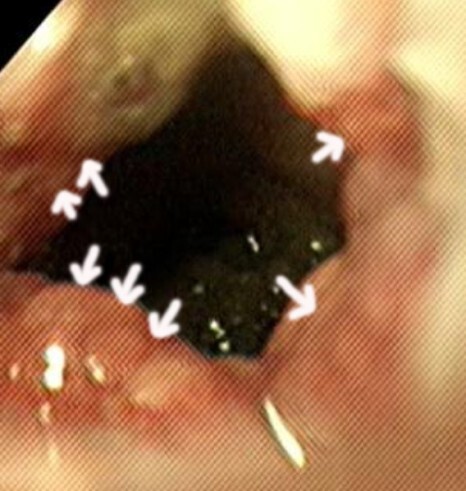

증상 때문에 다시 내원하였고 내시경으로 협착 부위

확인 후 풍선확장술을 진행하였습니다.

시술 이후 내시경 검사에서 협착 부위에 약간의

출혈이 확인되었지만 수지검사상 협착 부위가

확인되지 않는 것을 확인 후 시술을 종료하였습니다.